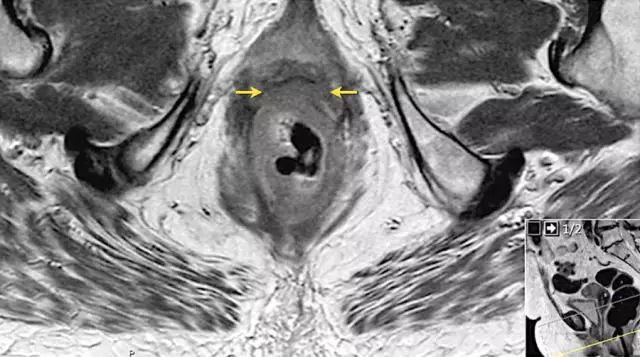

图 14 轴向 T2 加权图像上,沿着内脏腹膜有肿瘤向内生长(箭头)

图 15 同一患者腹膜转移的矢状图(箭头),在直肠内还有可疑的淋巴结